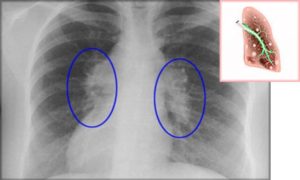

Для обнаружения легочных заболеваний в первую очередь используется флюорография. Эту процедуру необходимо проводить ежегодно, в основном она направлена на выявление ранней стадии туберкулеза. Однако опытный рентгенолог может выявить на снимке образовавшиеся плевральные спайки, которые выглядят тенями. Причем форма их не меняется в зависимости от вдоха и выдоха.

При необходимости дополнительно назначается рентген. Как правило, спайки располагаются в нижней части легкого. При этом будет более темная картинка, а также может быть частичная деформация грудной клетки и диафрагмы.

Определить наличие спаек в легких можно при помощи флюорографии. Этот метод исследования является наиболее достоверным. Дополнительно могут назначить рентген легких. Врач определяет наличие спаек по характерным темным пятнам, которые видны при получении рентгеновского снимка. Изменения могут также наблюдаться в диафрагме — она становится менее подвижной.

Самым распространенным методом диагностики легких является – флюорография. Но если врач подозревает, что у пациента есть спайки, то больной отправляется на рентген. По рентгеновскому снимку распознать синехию можно по мутным темным пятнам. Она выглядит, как теневое затемнение и неподвижна при вдохе и выдохе.

Плевродиафрагмальная спайка на снимке рентгена

Иногда выявляется деформация грудной клетки и диафрагмы. Чаще всего спаечный процесс отмечается в нижней части легкого. Такой вид спаек – плевродиафрагмальный, а вид спаек в верхней части – плевроапикальный.